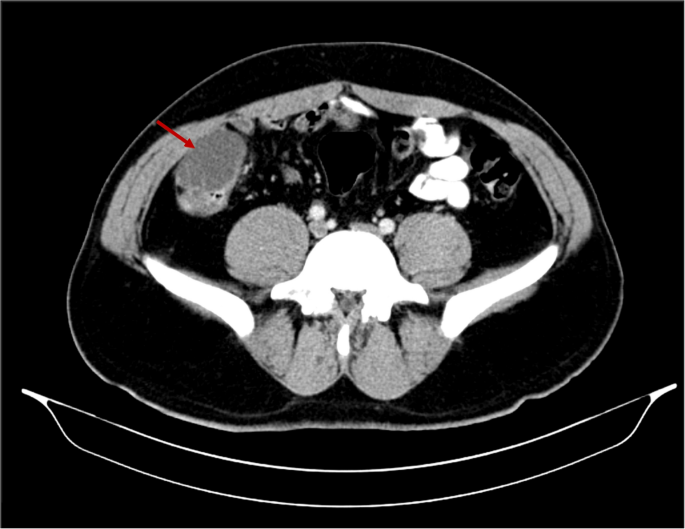

Upon reassessment post 10-day course, the patient stated that the pain decreased in severity but did not go away and was still causing discomfort. A follow-up abdomino-pelvic CT with IV and PO contrast was performed and revealed an increase in the size of the cystic collection to 4.3 × 5.5 cm, with enhancement of the previous fat stranding, adherence to the cecal wall medially, and to the abdominal wall laterally, with the suggestion of a possible complicated appendagitis or duplicated cyst as the main cause (Fig. 1). No mass lesion, adenopathy, or ascites was noted. The decision was taken to go for diagnostic laparoscopy. After insufflation and pneumoperitoneum creation, a fixed mass was perceived on the cecum, severely adherent to the cecal wall, and to the lateral peritoneal reflection, which was inconsistent with inflammatory lesions such as diverticulitis or epiploic appendagitis (Fig. 2). Successful dissection of the mass from the lateral wall was accomplished using scissors and cautery (Fig. 3). However, upon dissecting the mass from its connection to the cecal wall, great difficulty was experienced, with failure of the dissection, especially after noticing the presence of a common vessel supplying the cecum and the cyst at the same time. As a result, an ileocecectomy was decided by exteriorizing the ileum, cecum, and the cyst through a 6 cm RLQ incision and applying a mechanical side-to-side ileocolic anastomosis, then returning the bowel to the peritoneal cavity, followed by deflation and closure (Fig. 4). Postoperatively, the patient had mild pain with no major complaints, and was discharged home four days later.

Cystic collection to 4.3 × 5.5 cm, with fat stranding and adherence to the cecal wall medially and the abdominal wall laterally